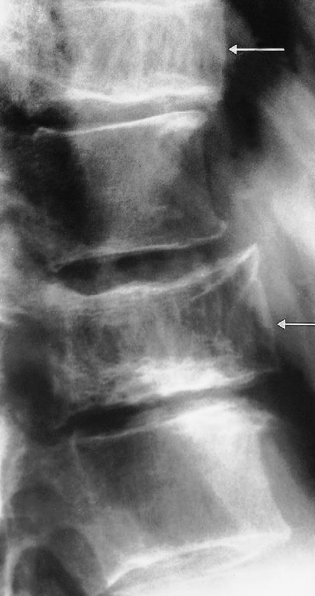

Modality X-ray lumbar spine (lateral view)

Findings Anterior displacement of L4 on L5 is visible. In addition, there is degenerative disk disease with narrowing of the L4–L5 disk space.

Diagnosis Disc Space Narrowing e.g. degenerative disc disease; Associated with endplate sclerosis and osteophytes